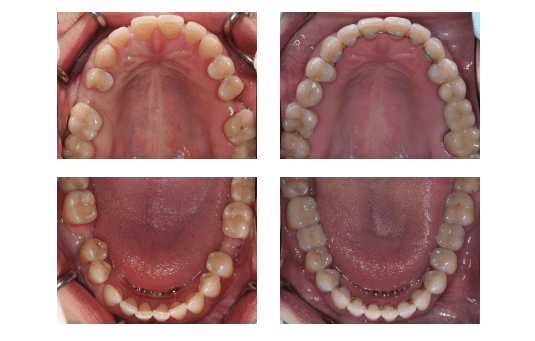

Пациентка, 37 лет, обратилась к ортодонту с жалобами на наличие промежутков между зубами на обеих челюстях, на «неправильное» положение некоторых зубов. Также ее беспокоил появившийся за последнее время наклон зубов «вперед».

Для анализа диагностических данных были привлечены пародонтолог, стоматолог-терапевт, имплантолог и стоматолог-ортопед, т.к. отсутствие нескольких зубов, дефекты твердых тканей зубов, заболевание пародонта сопутствовали основной патологии. Был составлен план комплексного стоматологического лечения. Предортодонтическая подготовка заключалась в лечении тканей пародонта и устранении дефектов твердых тканей.

В процессе ортодонтического лечения устранялись промежутки между зубами, излишний наклон зубов, скученность. В боковых отделах верхнего и нижнего зубных рядов, на месте отсутствующих зубов, создавались адекватные промежутки для будущей имплантации и протезирования.

Ситуация после 4-х месяцев ношения брекет-системы. Улучшается форма зубных рядов и положение зубов.<.p>

Промежутки между зубами устранены

В окончательном периоде ортодонтического лечения проводилась детализация положения отдельных зубов и улучшение межзубных контактов.

После дебондинга брекетов установлены несъемные ретейнеры.

Деффекты восстановлены металлокерамическими реставрациями.

Комплексный подход в лечении пациентки позволил успешно решить все стоматологические проблемы. Установка имплантов на этапах ортодонтического лечения сократила общую продолжительность лечения без ущерба для остеоинтеграции. Протезирование полностью восстановило жевательную функцию с максимальным эстетическим результатом. Плотные межзубные контакты, правильное положение осей зубов по отношению к базису челюсти, адекватное распределение жевательной нагрузки создают условия для ремиссии пародонтита.

Пациентка полностью удовлетворена функциональным и эстетическим результатом лечения: